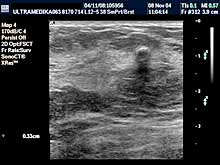

- ako postoji promena i mikrokalcifikacija obavezna je primena: 3D Sono CT i 3D CPA i Broad

band-CD i CPD,

- ako postoji sumnja na zloćudnu promenu pored navedenog

potrebna je procena morfologije i krvnih sudova regionalnih limfnih

žlezda.

- XRes,